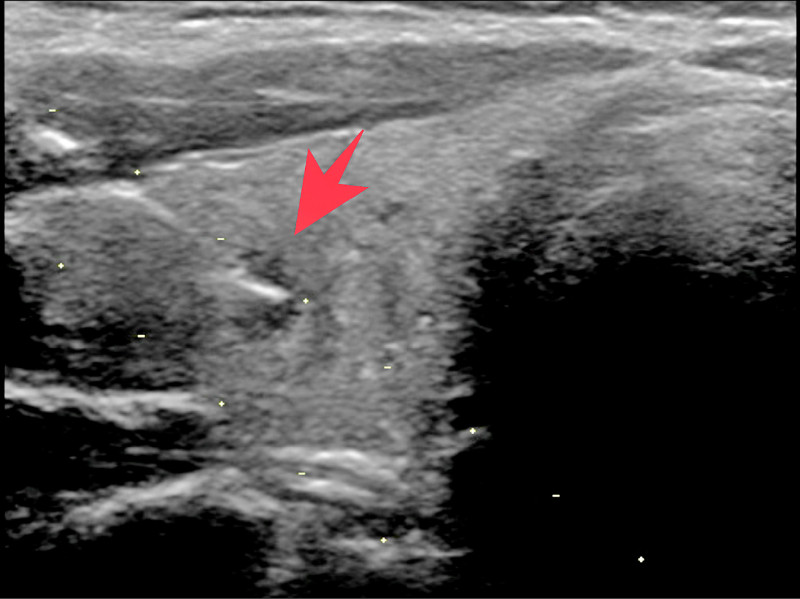

39歲陳先生參加公司健檢時,特別安排甲狀腺超音波檢查,意外發現右側甲狀腺有1個小結節(圖1),隨後轉診至新陳代謝科,接受細針穿刺檢查,確診為「甲狀腺微小乳突癌」(圖2),經手術切除右側甲狀腺及峽部,術後恢復情況良好。

經再次檢視影像,發現結節有多個異常特徵,包括結節高度大於寬度、結節是實心、結節是低回音等,雖然結節內沒有鈣化點、邊緣也規則,但還是高度懷疑是「甲狀腺微小乳突癌」,隨後在超音波導引下,進行細針穿刺檢查,1星期後報告出爐後,果然證實是甲狀腺乳突癌。